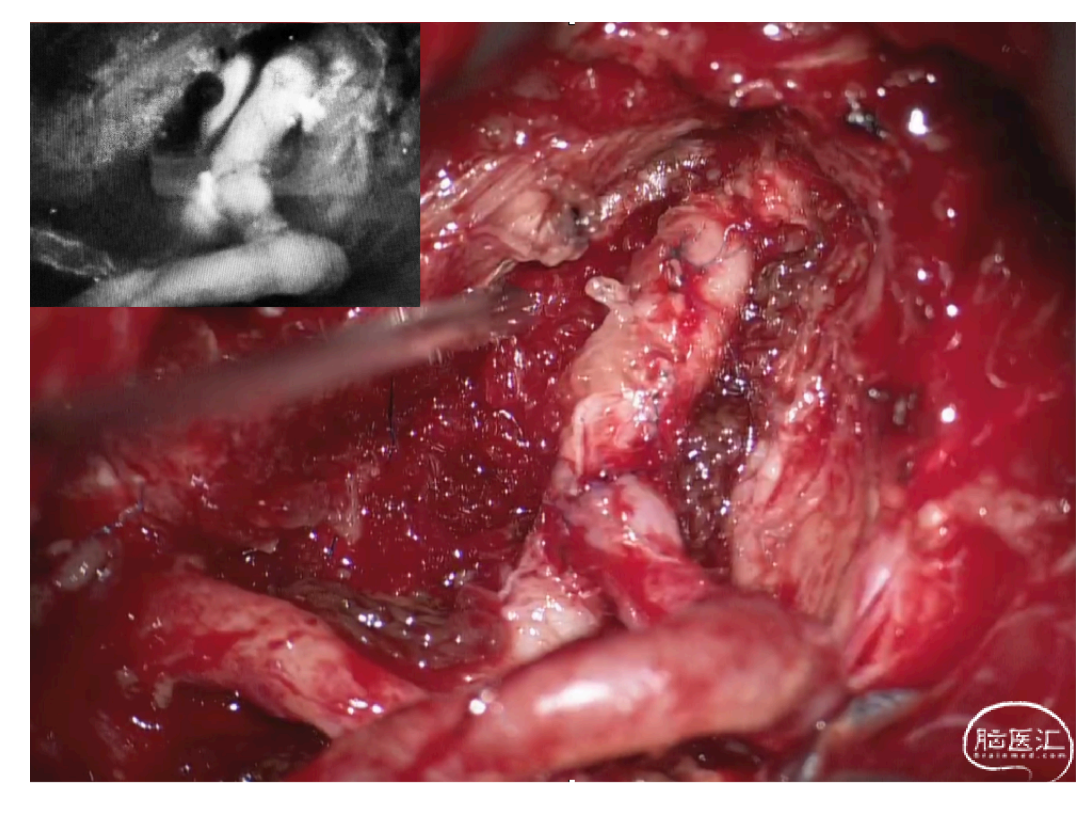

本期脑医汇为大家分享:天津市环湖医院【佟小光教授】的精彩病例内容:颈横动脉-椎动脉吻合治疗双侧椎动脉闭塞,欢迎阅读和分享!病例视频观看点击图片观看视频讲者:佟小光讲题:颈横动脉-椎动脉吻合治疗双侧椎动脉闭塞病例内容截图声明:脑医汇旗下神外资讯、神介资讯、神内资讯、脑医咨询、Ai Brain 所发表内容之知识产权为脑医汇及主办方、原作者等相关权利人所有。投稿邮箱:NAOYIHUI@163.com 未经许可,禁止进行转载、摘编、复制、裁切、录制等。经许可授权使用,亦须注明来源。欢迎转发、分享。